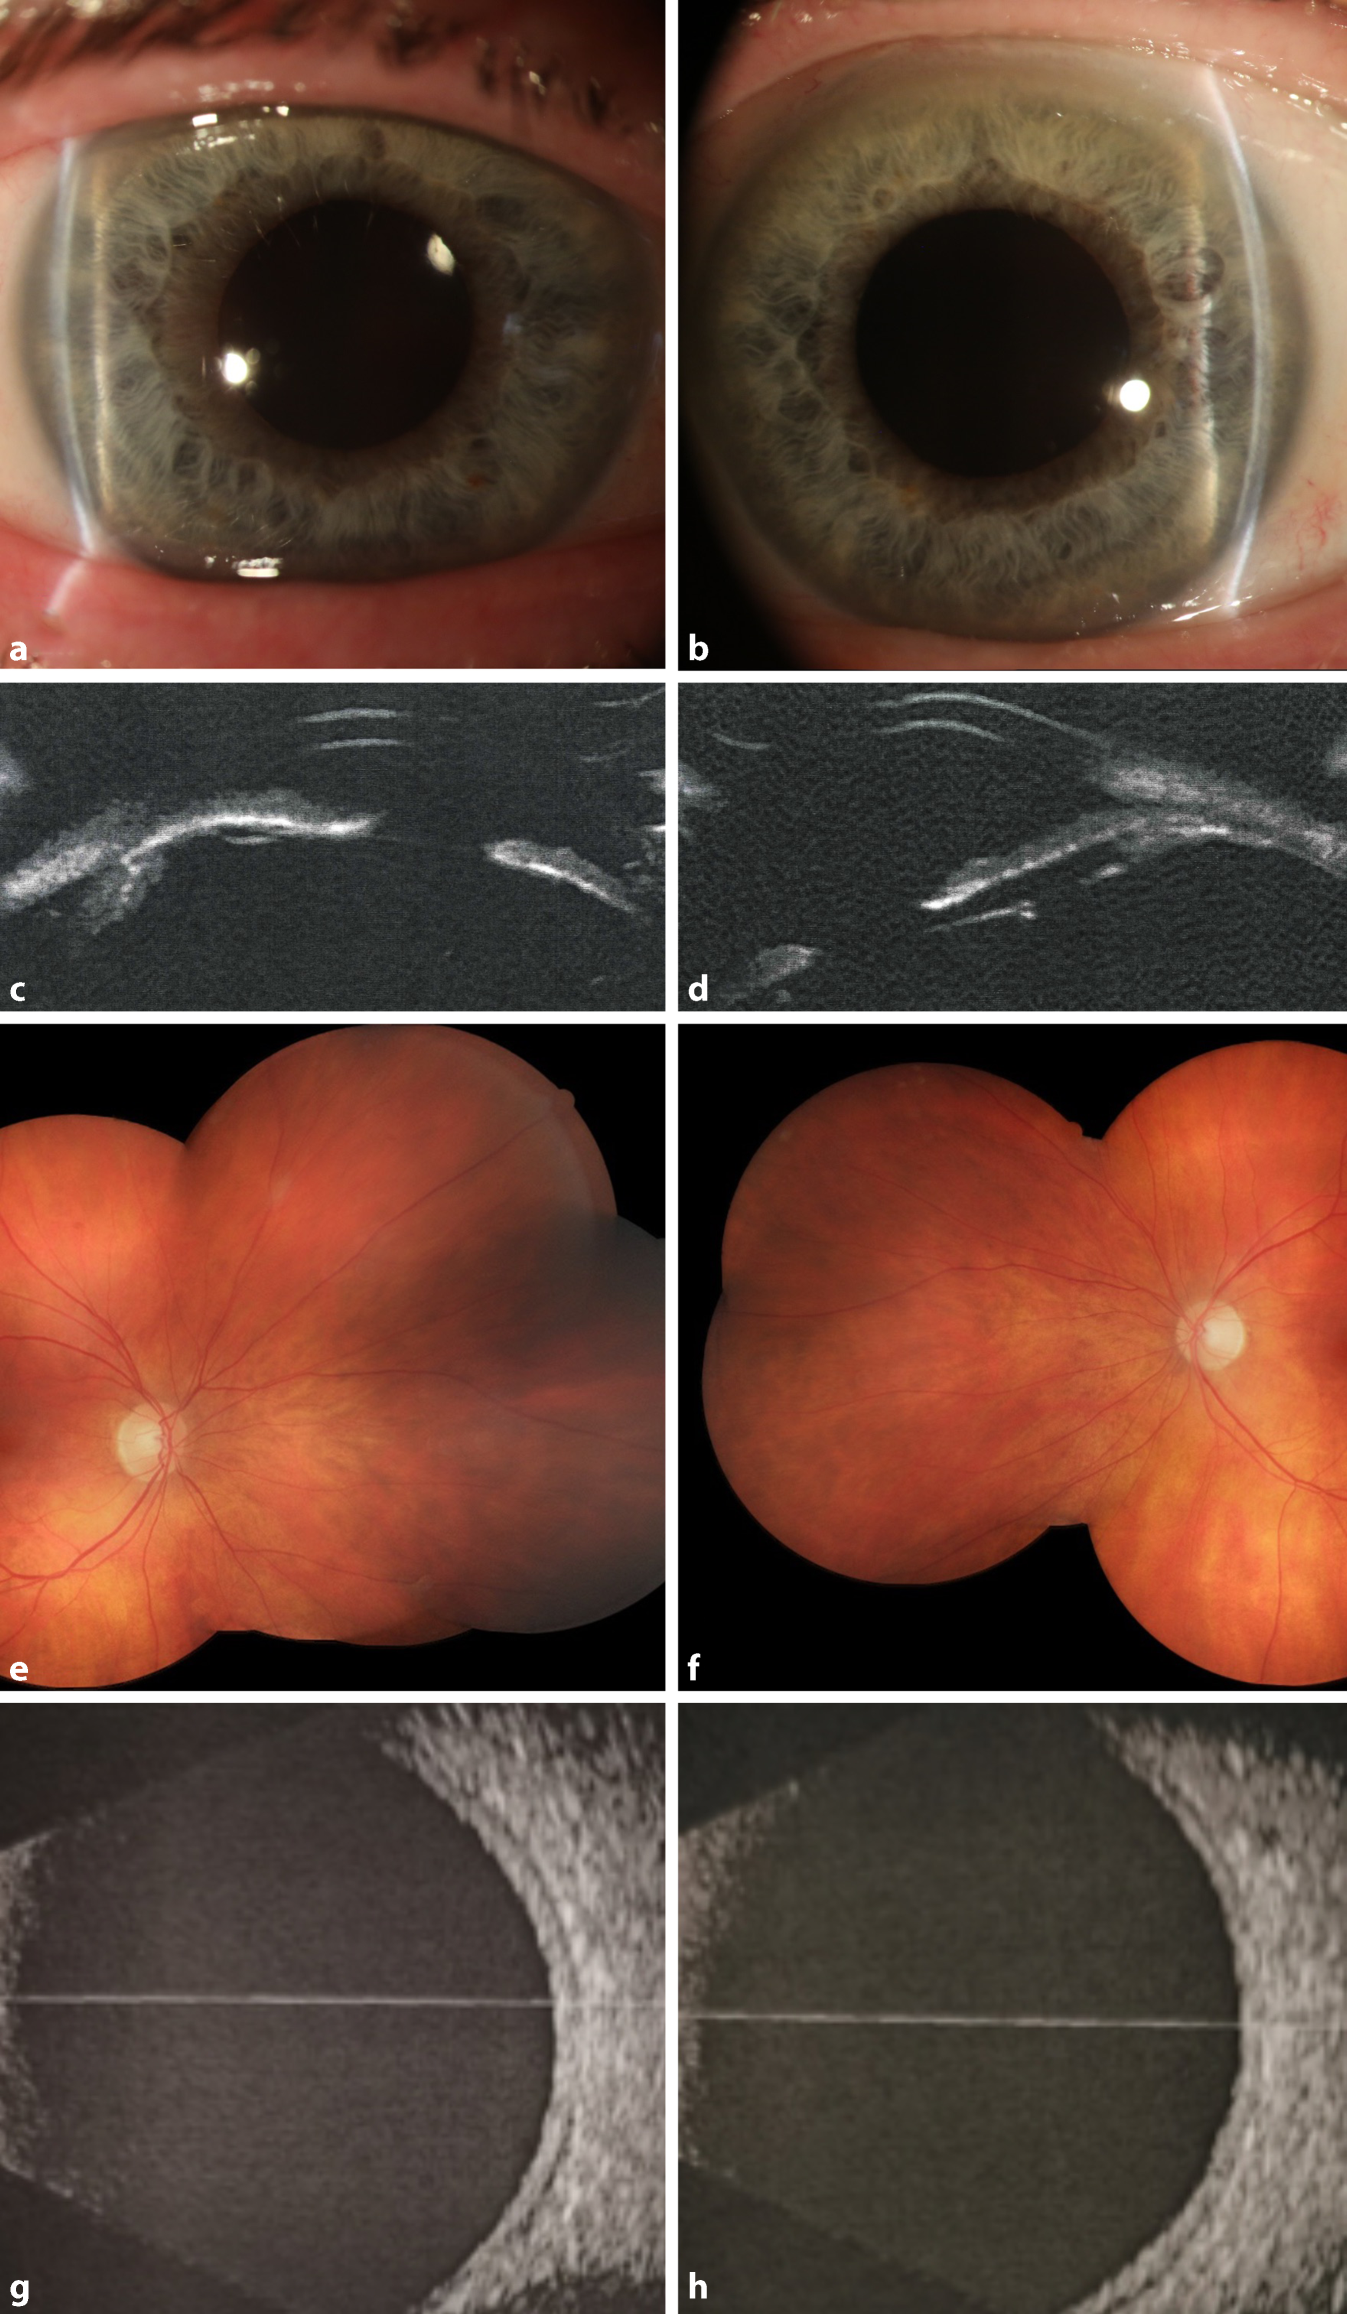

Abb. 2

B‑Scan-Sonographie des hinteren Augenabschnitts des rechten (c) und linken (d) Auges mit deutlicher Aderhautabhebung vor initialer Drucksenkung. Der rechte (a) und linke (b) Fundusbefund zeigten nach initialer Drucksenkung eine bilaterale periphere nasale Aderhautabhebung

Eine initiale systemisch-intravenöse Drucksenkung erfolgte mit Acetazolamid 500 mg und Mannitol (15 %) 300 ml sowie beidseits lokal mit Timolol 0,5 %, Apraclonidin 5 % und Prednisolon 1 %. Unter der genannten Therapie zeigte sich nur eine unzureichende Drucksenkung bei Zunahme der Aderhautschwellung, sodass die Arbeitsdiagnose überdacht werden musste. Acetazolamid wurde im Weiteren als Ursache für ein bilaterales uveales Effusionssyndrom mit sekundärem iridokornealem Engwinkelglaukom angenommen und daher abgesetzt. Dementsprechend erfolgte die weitere systemische Therapie mit einer erneuten Einmalgabe von Mannitol (15 %) 300 ml intravenös und Prednisolon 100 mg per os täglich. Hierunter verbesserte sich der klinische Befund über 3 Tage allmählich. Der Augeninnendruck konnte rechts auf 7 mm Hg und links 9 mm Hg gesenkt werden. In der Fundoskopie zeigte sich noch eine bilaterale periphere Aderhautabhebung (Abb. 2a, b). Der bestkorrigierte Dezimalvisus stieg auf rechts 0,8 und links 0,9 an, die Konfiguration der Vorderkammer normalisierte sich, und die Myopisierung zeigte sich rückläufig. Die systemische und lokal drucksenkende Therapie wurde beendet.

In der Verlaufskontrolle zeigte sich nach 1 Woche beidseits ein regelrechter sonographischer und fundoskopischer Befund des hinteren Augenabschnitts (Abb. 3). Die Vorderkammertiefe betrug rechts 4,39 mm und links 4,37 mm bei einem Augeninnendruck von rechts 10 mm Hg und links 11 mm Hg. Der unkorrigierte Dezimalvisus betrug nun beidseits 1,0. In der nochmals durchgeführten Ultraschallbiomikroskopie offenbarte sich nun beidseits eine Plateau-Iris-Konfiguration (Abb. 3c, d).

Abb. 3

Befund in der Verlaufskontrolle nach 10 Tagen. Spaltlampenmikroskopie des rechten (a) und linken (b) Auges mit tiefer Vorderkammerkonfiguration. In der Ultraschallbiomikroskopie des vorderen rechten (c) und linken (d) Augenabschnitts offenbart sich eine Plateau-Iris. Am hinteren Augenabschnitt zeigt sich die Aderhaut, Befund entsprechend am rechten und linken Auge, in der Fundoskopie (ef) sowie in der B‑Scan-Sonographie (gh) flach anliegend